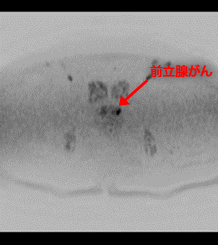

骨シンチグラフィー

進行した前立腺がんは、全身の骨にも転移します。骨への転移の有無を調べるためには骨シンチグラフィーを行います。

骨シンチグラフィーは、放射性物質ががんの転移のある骨に集まる性質を利用した検査です。

放射性物質を静脈注射したあと、シンチグラフィーで全身の骨を撮影すると、がんの転移のある骨の部分が黒く映ります。